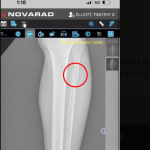

エリオットのレントゲン写真(@TElliott125より)